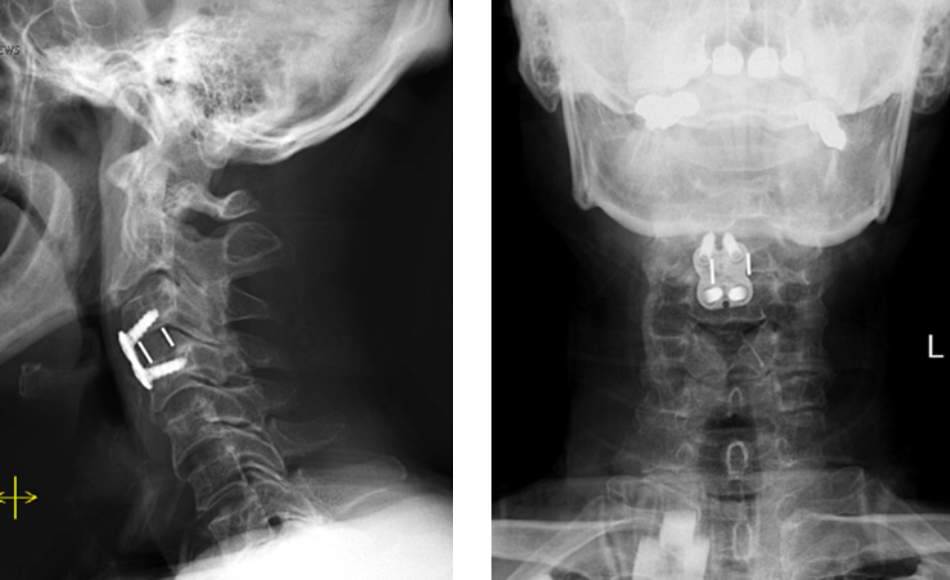

Dr. Imani performed an Anterior Cervical Discectomy and Fusion to remove the pressure of the herniated disc from compressing the spinal cord and stabilizing the spinal column with a fusion of the C3/C4 disc space.

After Dr. Imani’s surgery, the patient is making a full recovery. He is able to walk and move both arms/hands.

Figure 2. Lateral and AP cervical spine x-rays s/p ACDF